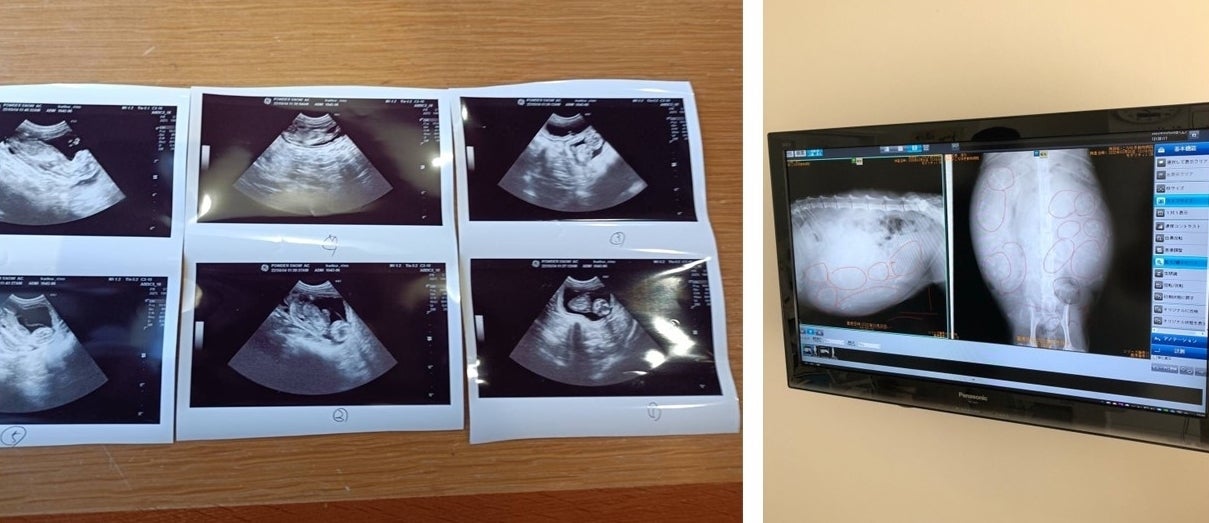

そんななか、この春に妊娠中期で保護された母猫を預かることになりました。そして出産まで見守り、4月1日の5つ子の出産に立ち会いました。

全員元気にお腹の中で育ち

無事に生まれました!

死産も生まれてすぐに亡くなることもなく、全員無事に生まれた5つ子。そして2か月以上経った今でもみんな元気で同じようにすくすく大きく成長しています。